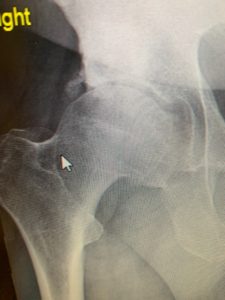

Above is the hip in question – compared to my almost perfect Left Hip pictured below. My Dr. asked how I’m even able to walk right now……